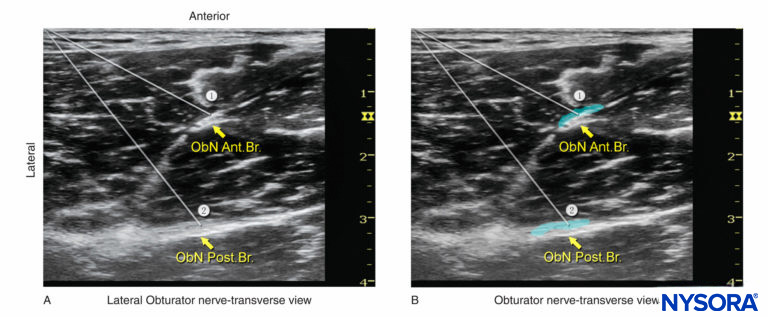

The interfascial approach is performed at the level of the femoral crease. With this technique, it is important to identify the adductor muscles and the fascial planes in which the individual nerves are enveloped. Color Doppler can be used to visualize the obturator arteries located near the nerve branches in order to avoid puncturing them, although they are not always visible.

The US transducer is placed to visualize the femoral vessels. The transducer is advanced medially along the crease to identify the adductor muscles and their fasciae. The anterior branch is sandwiched between the pectineus and adductor brevis muscles, whereas the posterior branch is located in the fascial plane between the adductor brevis and adductor magnus muscles. The block needle is advanced to initially position the needle tip between the pectineus and adductor brevis (Figure 6a).

At this point, 5–10 mL of local anesthetic solution is injected.

The needle is advanced farther to position the needle tip between the adductor brevis and adductor magnus muscles, and another 5–10 mL of local anesthetic solution is injected (Figure 6b). It is important for the local anesthetic solution to spread into the interfascial space and not be injected into the muscles. Correct injection of local anesthetic solution into the interfascial space results in an accumulation of the injectate between the target muscles. The needle may have to be repositioned to allow for precise interfascial injection.

FIGURE 6. (A) Needle paths (1, 2) required to reach the anterior branch (ant. br.) and posterior branch (post. br.) of the obturator nerve (ObN). (B) Simulated dispersion of local anesthetic (blue-shaded areas) to block the anterior and posterior branches of the obturator nerve. In both examples, an in-plane needle insertion has been used.

Alternatively, the cross-sectional image of obturator nerve branches can be obtained by scanning 1–3 cm distal to the inguinal crease on the medial aspect of thigh. The nerves appear as hyperechoic, flat, thin, fusiform-shaped structures invested in the fascia of the adductor muscles. The anterior branch is located between the adductor longus and adductor brevis muscles, whereas the posterior branch is located between the adductor brevis and adductor magnus muscles. An insulated block needle attached to the nerve stimulator is advanced toward the nerve with either an out-of-plane or in-plane trajectory. After eliciting contraction of the adductor muscles, 5–7 mL of local anesthetic is injected around each branch of the obturator nerve (see Figure 6b).